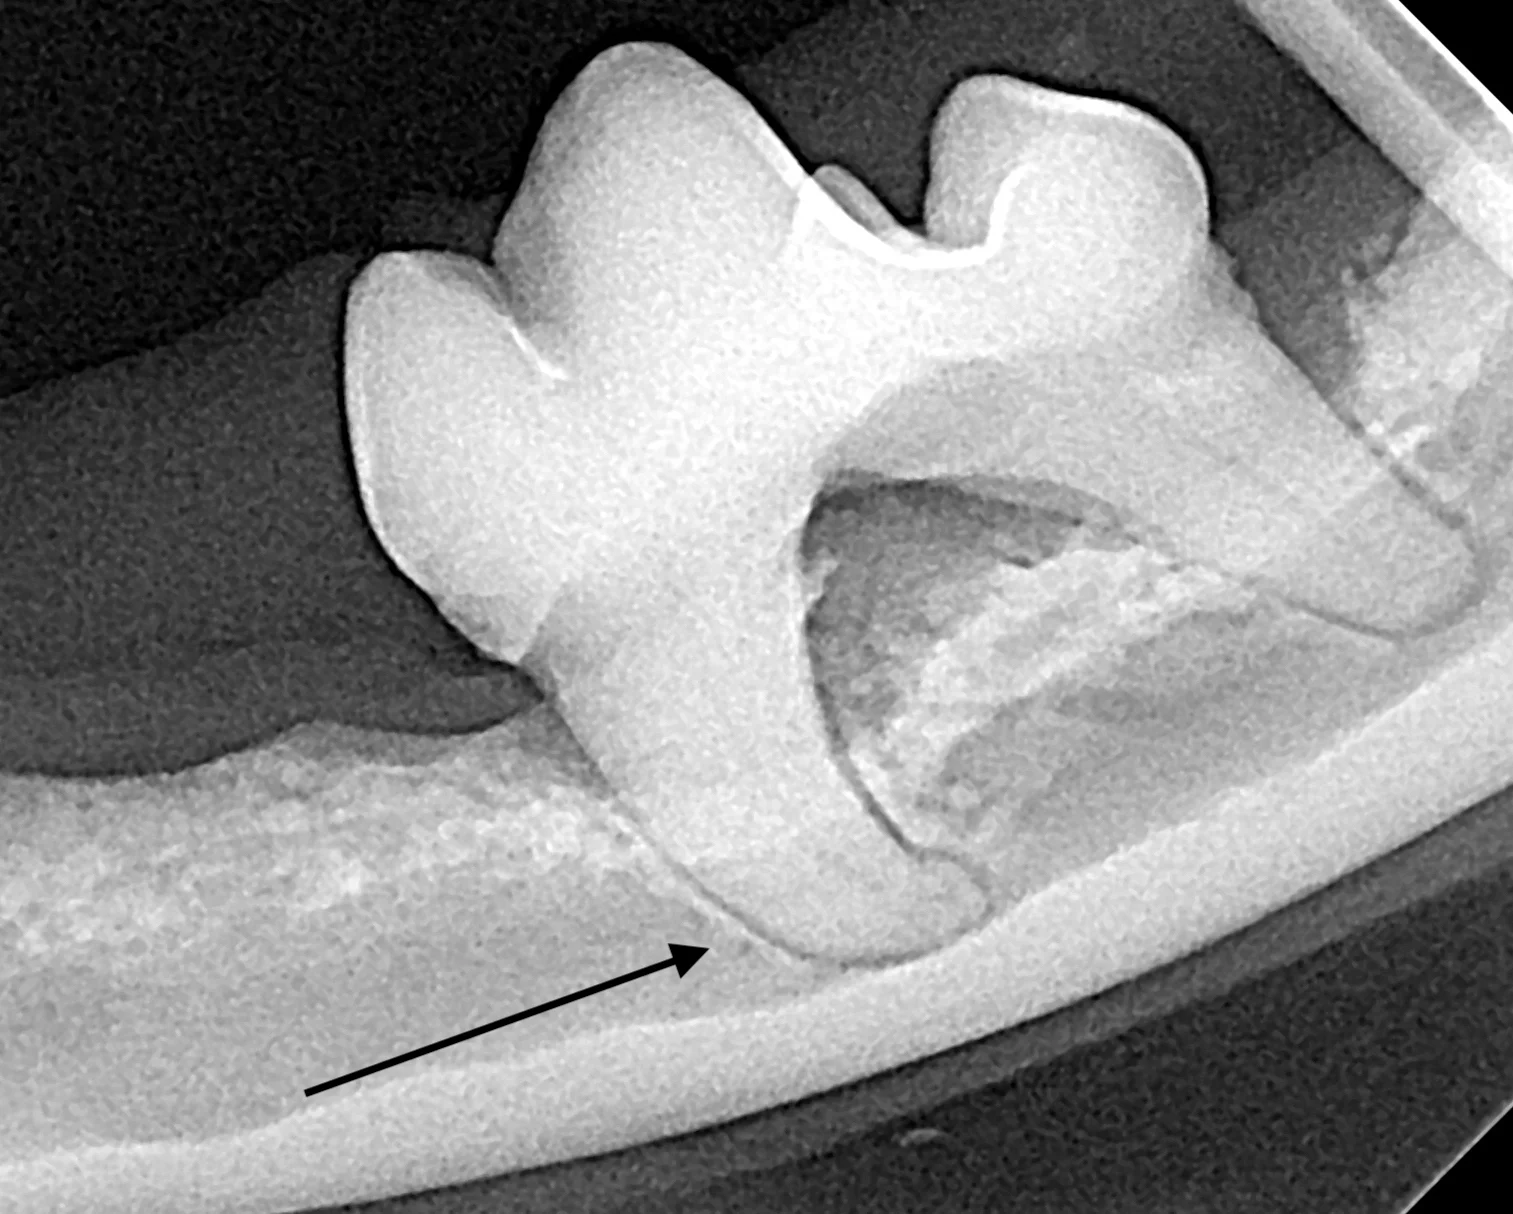

Iatrogenic fracture of the jaw can be a serious complication of surgical extractions and is most commonly associated with surgical extraction of mandibular canine teeth in dogs and cats and mandibular first molar teeth in dogs (Figure 10). These extractions can be difficult to perform, as the root apexes are often located in close proximity to the ventral cortex of the mandible, possibly leading to significant bone loss when severe disease is present and increasing the risk for iatrogenic fracture (Figure 11).

Pathologic fracture (arrow) secondary to severe periodontal disease of the right mandibular first molar tooth in a dog

Severe periodontal disease affecting the right mandibular first molar tooth in a dog. Careful extraction technique is necessary to extract the tooth without creating an iatrogenic fracture.

Preoperative intraoral radiographs are critical for assessing fracture risk, especially prior to surgical tooth extraction, and can be used to modify the procedure or refer a patient with high fracture risk to a board-certified veterinary dentist.